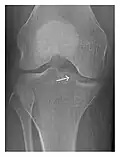

Figure 1: A 56-year-old woman presenting with left knee pain after a fall. (a) Initial anteroposterior radiograph was considered normal, however, subtle cortical disruption of the anterior rim of the medial tibial plateau, medial to the tibial spine, is noted (arrow). (b) Coronal T1-weighted MRI confirms the cortical disruption (arrow) and shows extensive fracture through the proximal tibia. (c) Coronal proton density-weighted image with fat saturation shows extensive edema in the subchondral bone. Note also hypersignal adjacent to the medial collateral ligament corresponding to a grade I sprain (arrowheads).[1]

-

a -

b -

c